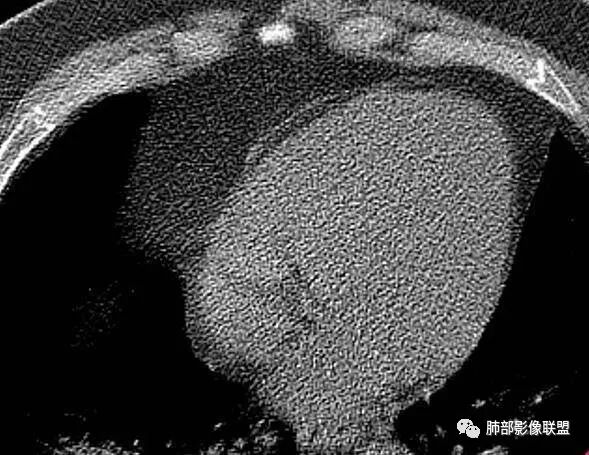

长沟流月去无声:第三点有意见这个人心脏大,左室供血很不好

南边:南边:不大啊冬瓜:熊老师不会考虑病毒感染,爆发性心肌炎吧南边:这个就不敢说淘时光:左心室心腔饱满,室间隔向右室侧有些移位,感觉左室有增大

长沟流月去无声:这个左室心肌都薄了南边:没有做增强啊长沟流月去无声:可以提示大家去看一下流感病毒性肺炎重症,WHO和卫生部都出过指南,建议你们仔细看看指南里危险人群一节,是哪几个